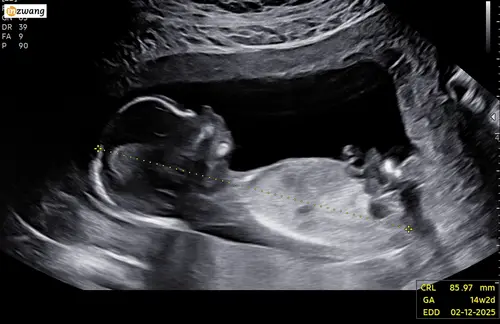

Heel benieuwd of jullie het kunnen zien aan de hand van nub.. Ik ben er niet goed in namelijk :))